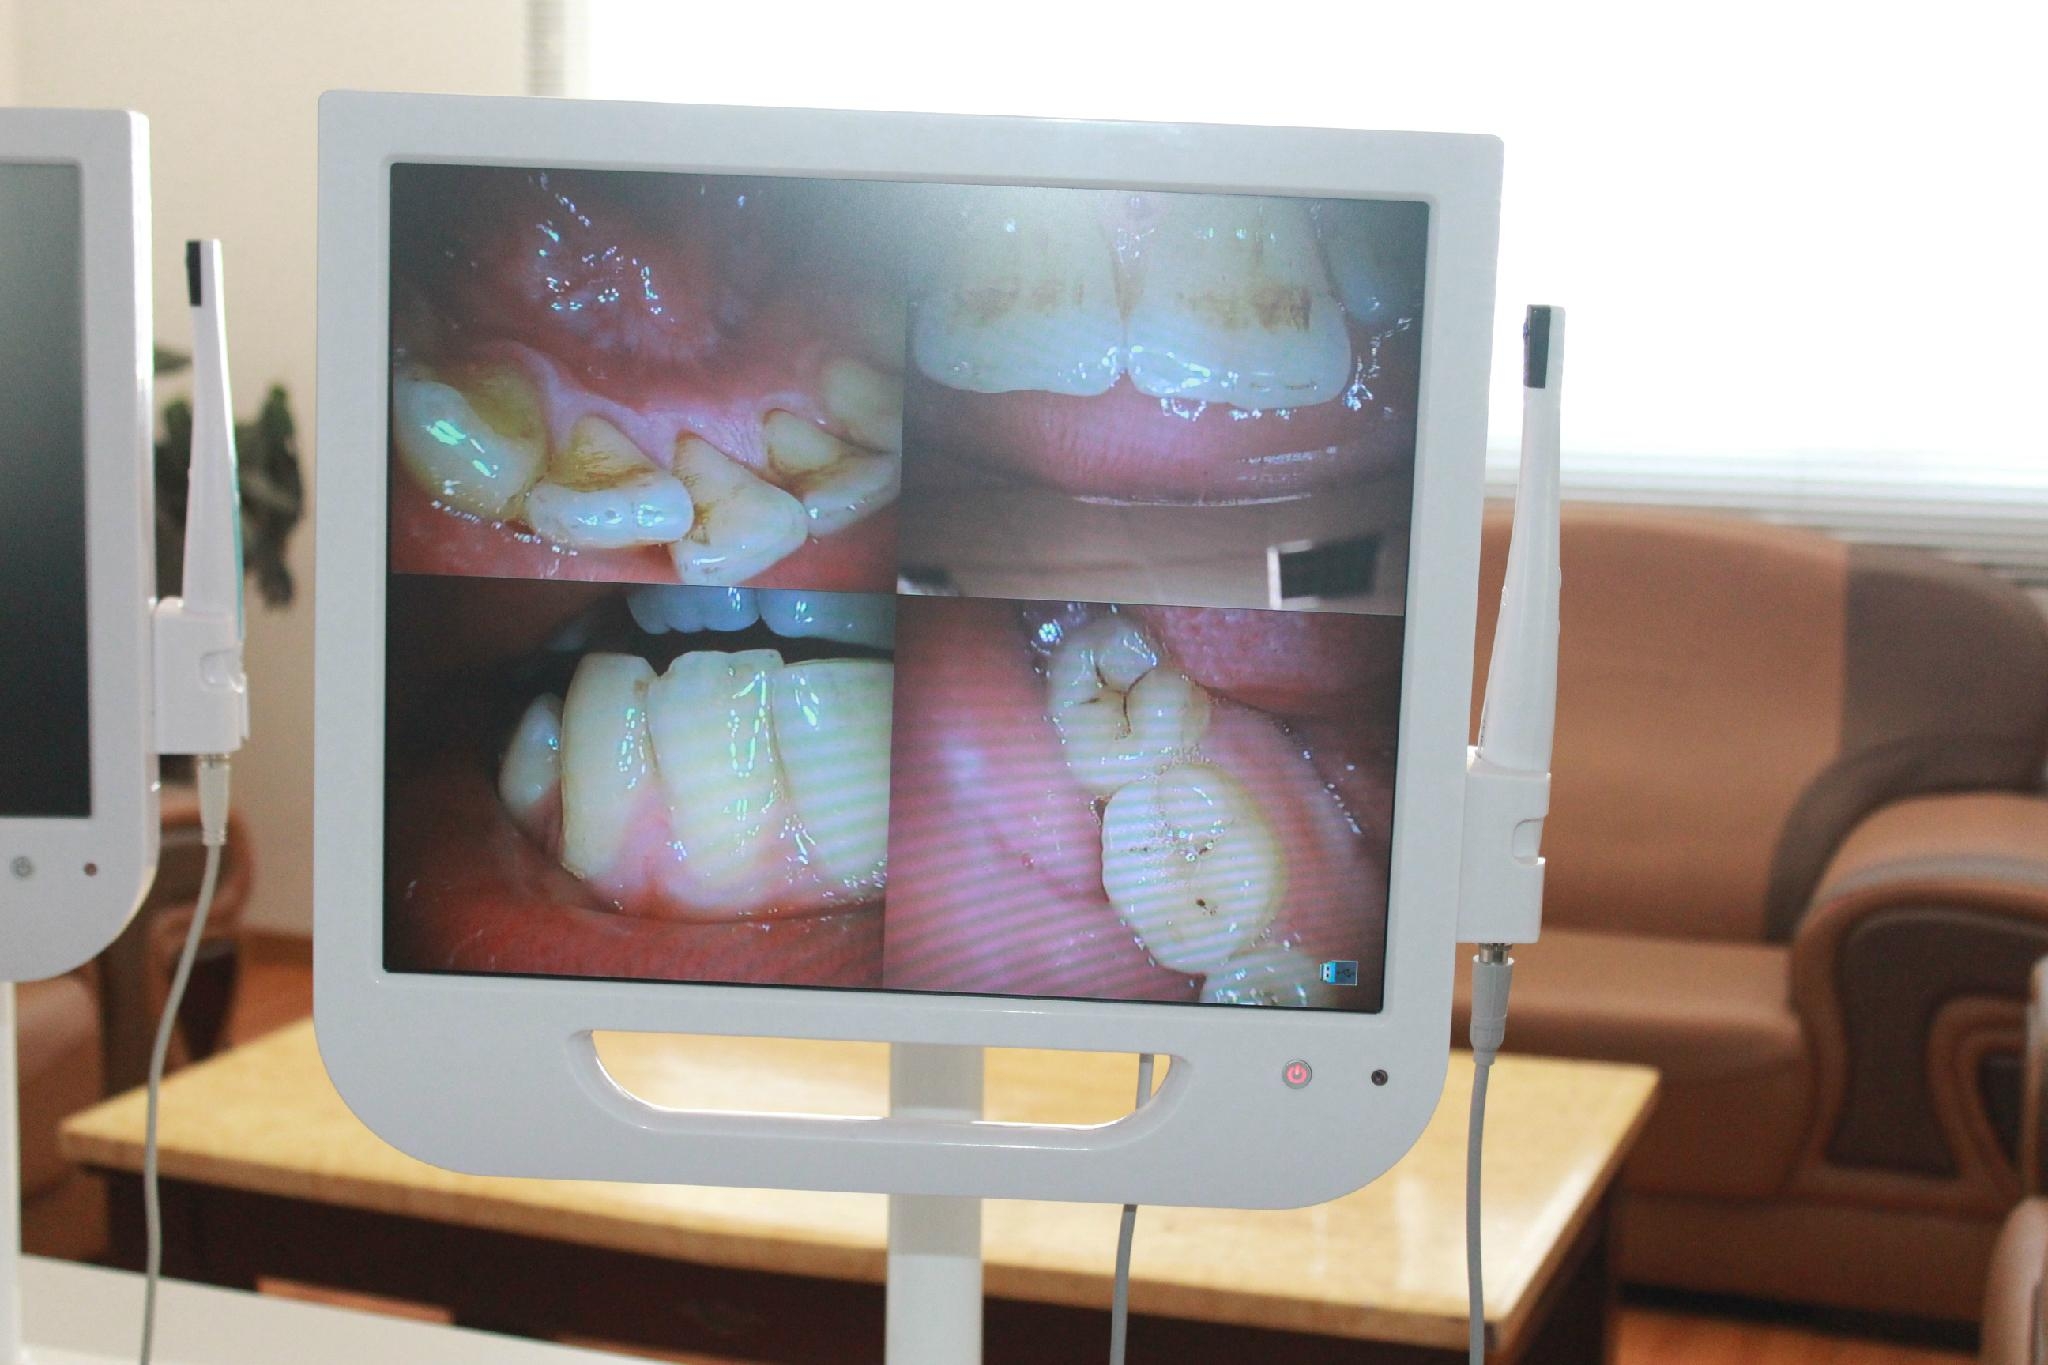

The Simple Tool For Patient Education

17 Inch monitor Touch Screen with built in intra oral camera Combining the latest video technologies, is an exceptional tool for patient education, higher case acceptance, and improved patient communication.

Camera |

1/4 SONY CCD |

Pixels |

5.0Mega pixels |

Lamp |

6 White color LED lamp |